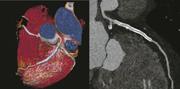

Coronary CTA on the Somatom Force produces high-resolution stent imaging with a 0.18 second scan at 70 kV exposing the patient to just 0.43 mSv. The patient's heart rate varied between 58 to 70 bmp during the exam. Color image shows two long stents. The curved MPR image in grayscale shows the details in the LAD stent. Image provided by Siemens Healthcare, copyright Institut fur Klinische Radiologie und Nuklearmedicin, Universitatsmedizin Mannheim Medizinische Fakultat Mannheim der Univesitat Heidelberg

Siemens billed its Somatom Force as the next generation in dual-source CT. Successor to the Somatom Definition Flash, the company’s previous top-tier CT, Force features two generators that — like the generators on its predecessor — fires X-rays independently at variable energies. Force is so fast, however, that it can image the adult chest in a second, eliminating the need to breathhold, and freeze a human heart pumping at 90 beats per minute by merging the two imaging chains to create a 50 cm (nearly 19.7-inch) field of view. Alternatively the two imaging chains, like those on the Flash, can be tuned to separate energies to differentiate among tissues or materials, as in visualizing iodinated contrast as it flows through the coronaries or accumulates in varying amounts in benign versus malignant masses, such as those in the kidney.

The two X-ray generators on Siemens’ Somatom Force can be pumped at low voltage (as low as 70 kVp) to deliver low-dose scans. Dose can be reduced further using the company’s SAFIRE software. This combination allows Somatom Force to scan the lungs at half the dose of comparable systems, according to Siemens, making this 510(k)-pending technology ideal for lung cancer screening, which could soon enter mainstream medical practice in the United States.